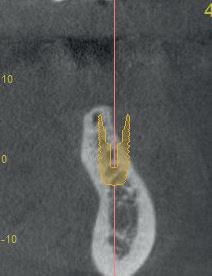

In een eerder artikel in Dentista (2019 issue 5) met de titel ‘Champignon of tulp?’ schreven we dat op basis van wat wij aan complicaties krijgen verwezen, het erop lijkt dat men ervan uitgaat dat overhang bij restauraties op implantaten geen probleem is. Gezien de bekende negatieve effecten van overhangende restauraties op het parodontium bij natuurlijke gebitselementen, is het echter niet verrassend dat implantaatgedragen suprastructuren met een paddenstoelachtige vorm problemen veroorzaken. In feite is het falen bij deze vormgeving al vanaf het ontwerp ingebouwd (afbeelding 1a-d).

In een meer recent artikel in Dentista (2020 issue 4), getiteld ‘De ideale vorm’, werd benadrukt dat de ‘emergence angle’ bij bone-level implantaten een belangrijke factor is in de ontwikkeling van peri-implantaire ontstekingen. Retrospectief onderzoek toont aan dat de prevalentie van peri-implantitis significant hoger is bij een emergence hoek groter dan 30 graden, vergeleken met abutments waarbij deze hoek kleiner is dan 30 graden. Recent werd dit opnieuw onderbouwd in een preklinische studie, waarin restauraties werden geplaatst met een emergence-profiel variërend van 20, 40, 60 of 80 graden (Strauss et al., 2024). Na 24 weken bleek dat grotere restauratieve hoeken leiden tot meer marginaal

botverlies. De auteurs concluderen daarom dat het verstandig is om de hoek zo smal mogelijk te houden, bij voorkeur onder de 40 graden. In de praktijk blijkt echter dat het niet altijd mogelijk is om een zo klein mogelijke restauratiehoek te gebruiken. Bijvoorbeeld wanneer er sprake is van een beperkte intermaxillaire ruimte. Om goed uit te komen met de suprastructuur zou dan een grotere restauratiehoek gebruikt moeten worden.

Bij bone-level implantaten met platform-switching is de diameter van het abutment op implantaat niveau kleiner dan die van het implantaat. Hierdoor is het risico groter dat, om occlusaal voldoende breedte te verkrijgen, er een te grote emergence angle ontstaat, wat resulteert in een te bolle kroon. Daarom is het bij de keuze voor een platform-switch implantaat in de basis essentieel om ofwel een implantaat met een grotere diameter te selecteren, ofwel het implantaat relatief dieper te plaatsen. Dit helpt om een optimale emergence te verkrijgen met een geschikte hoek en bolling vanaf het abutment naar de implantaatkroon.

Voor tandartsen en tandtechnici is het verleidelijk om de suprastructuur te modelleren naar de oorspronkelijke vorm van het verloren gegane element (zie figuur 1). Als de beschikbare botbreedte het toelaat, is het daarom wenselijk om in de molaarstreek

1a-d. Een mooi vormgegeven kroon op element 47, maar deze ligt als een balkon bovenop de gingiva, waardoor het implantaat niet te sonderen is – laat staan dat de patiënt het goed kan reinigen.

een implantaat met een grotere diameter te plaatsen. In veel klinische situaties is dit echter niet mogelijk, waardoor een aangepaste vormgeving overwogen moet worden. Onze boodschap in de vorige twee artikelen was: denk in dergelijke gevallen in termen van een ‘premolaar’. Deze vormgeving sluit beter aan bij de afmetingen van een implantaat en biedt een voorspelbaardere langetermijnprognose.